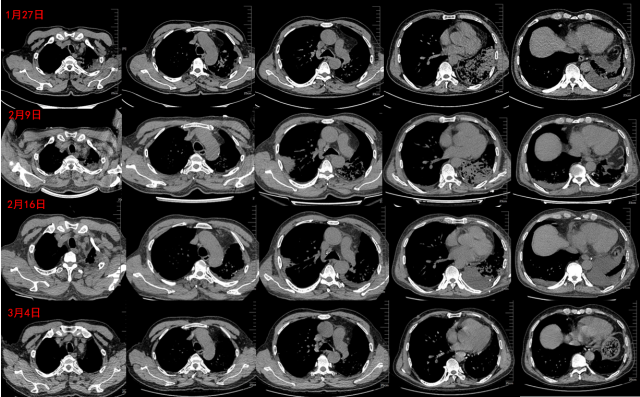

回顾患者影像学情况:1月27日患者入院,胸部CT以左肺病变为主,有液气胸表现。2月9日胸部CT可见右肺有大片新发病灶。经过甲泼尼龙治疗,2月16日胸部CT示左肺病灶明显吸收,3月4日门诊复查时可见胸部CT示双肺病灶均明显吸收(图10)

图片

图10  病程中患者影像学变化